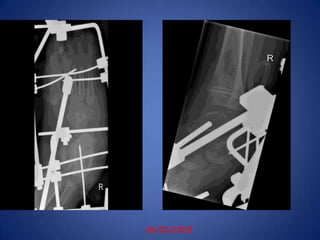

10/5/2009Post STR rt-3/M

28/10/2009

STR-dec2007(Sohar)JESS-28/10/2009KHTib AT-12/5/2010KHEXCELLENT RESULT18/4/2011